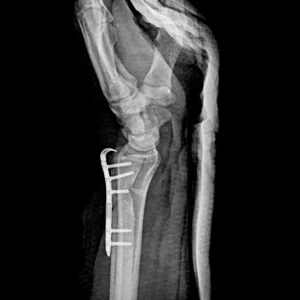

Placas para radio distal

RÁDIX Cubital

Indicaciones

Fracturas en la porción distal del cúbito simples y complejas

con compromiso intra y extra articular.

Materiales

Titanio para implantes

Presentación Set

Cubital Neutra 4-6 Orificios.

Para usar con:

» Tornillo Cortical Autotarrajante 2.7 mm – Titanio

» Tornillo de Bloqueo 2.4mm – Titanio